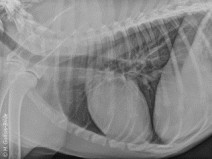

• Soirée : Les traumatismes abdominaux

Nous vous proposons une soirée sur les traumatismes abdominaux. Elle sera composée de deux grandes parties : comment identifier un traumatisme abdominal et comment mettre en place le traitement adapté.